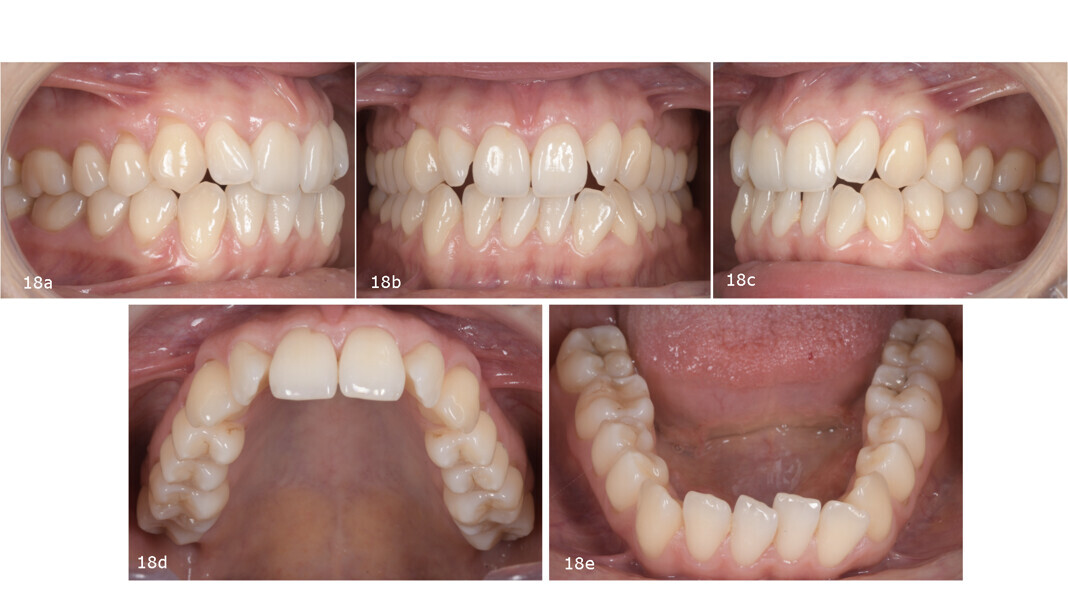

The occlusal analysis revealed a Class II Division 2 malocclusion, along with an anterior open bite tendency, insufficient overjet and overbite, maxillary and mandibular constriction, negative torque in both the posterior segments and maxillary incisors, a pronounced curve of Spee and severe crowding in both arches. The dental midlines were not centred. The mandibular midline deviated to the left, primarily owing to the inclination of the mandibular incisors. Despite having a favourable gingival biotype and adequate attached gingiva, the patient presented with localised gingival recession and abfraction lesions—most likely the result of occlusal instability and functional overload (Fig. 18).

The panoramic radiograph showed prior extraction of all third molars, localised root resorption of several teeth, generally good periodontal health and an atypical condylar morphology, suggestive of temporomandibular joint (TMJ) remodelling or degenerative changes (Fig. 19). The cephalometric radiograph and tracing revealed a mesobrachyfacial skeletal pattern and a tendency towards a Class II skeletal pattern (Fig. 20).